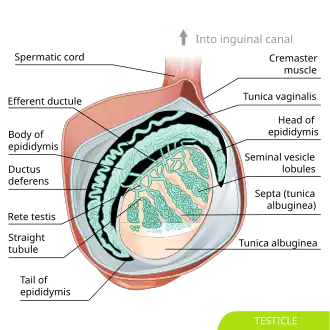

Diagram of inner structures of a human testicle (the labelling "seminal vesicle lobules" is incorrect and should be "testicular lobules" instead) | |

The testes are covered by a tough fibrous shell called the tunica albuginea.[5] Under the tunica albuginea, the testes contain very fine-coiled tubes called seminiferous tubules.[5] The tubules are lined with a layer of cells (germ cells) that develop from puberty through old age into sperm cells (also known as spermatozoa or male gametes).[5] The developing sperm travel through the seminiferous tubules to the rete testis located in the mediastinum testis, to the efferent ducts, and then to the epididymis where newly created sperm cells mature (spermatogenesis).[6] The sperm move into the vas deferens, and are eventually expelled through the urethra and out of the urethral orifice through muscular contractions.[6]

Within the seminiferous tubules, the germ cells develop into spermatogonia, spermatocytes, spermatids and spermatozoa through the process of spermatogenesis. The gametes contain DNA for fertilization of an ovum.[7] Sertoli cells – the true epithelium of the seminiferous epithelium, critical for the support of germ cell development into spermatozoa. Sertoli cells secrete inhibin.[8] Peritubular myoid cells surround the seminiferous tubules.[9]

Between tubules (interstitial cells) exist Leydig cells[10] – cells localized between seminiferous tubules that produce and secrete testosterone and other androgens important for puberty (including secondary sexual characteristics like facial hair), sexual behavior, and libido. Sertoli cells support spermatogenesis.[11] Testosterone controls testicular volume.

Immature Leydig cells and interstitial macrophages and epithelial cells are also present.